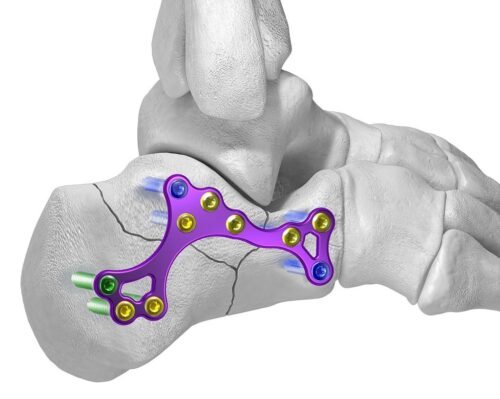

تثبيت الكسور بالشرائح والمسامير

ومع تقدم العلم اختلفت أنواع تثبيت الكسور جراحيًا تبعًا لنوع الكسر ومكانه ، وأيضًا تبعًا لعمر المريض وضمن هذه الأنواع هي تركيب الشرائح والمسامير الطبية، وتركيب المثبتات الخارجية والمسامير النخاعية ويحتاج الطبيب المعالج لعمل بعض الأشعات اللازمة لتحديد النوع المناسب لتثبيت الكسور.

ويقوم الطبيب بتثبيت الكسور والشروخ في جسم الإنسان بواسطة تركيب شرائح طبية ومسامير تساعد على التئام الكسر بشكل طبيعي وفي مكانه الصحيح مما يضمن للمريض استعادة حياته اليومية بشكل سريع وبدون ألم. وتناسب هذه الشرائح والمسامير بصفة خاصة الكسور القريبة من المفاصل.

ويتقبل جسم الإنسان هذه الشرائح والمسامير بشكل عادي فلا يعتبرها جسم غريب عنه أو يرفضها، وذلك لأن هذه الشرائح مصنوعة من عدة سبائك وهي: سبائك التيتانيوم وسبائك النيكل والكروم الممزوجة بالحديد وأيضًا سبائك الكوبالت.